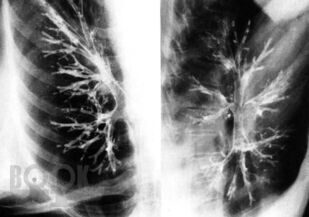

В монографии представлены важнейшие хронические заболевания легких у детей, рассмотрены вопросы терминологии и классификации этих болезней. Описаны клинические проявления различных форм хронической бронхолегочной патологии, даны критерии и современные методы диагностики. Отдельные главы посвящены хроническим воспалительным заболеваниям легких, врожденной и наследственной патологии, бронхиальной астме, интерстициальным болезням легких, грибковым поражениям бронхолегочной системы. Рассмотрены особенности течения туберкулеза при хронических неспецифических заболеваниях легких. Изложены принципы терапии хронических заболеваний легких у детей. Книга адресована педиатрам, пульмонологам, аллергологам, врачам общей практики, сотрудникам научно-исследовательских учреждений и учебных заведений.